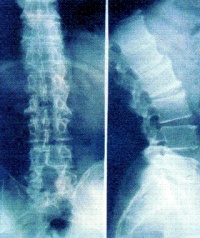

X线检查对AS的诊断有极为重要的意义,约98%~100%病例早期即有骶髂关节的X线改变,是本病诊断的重要依据。

早期X线表现为骶髂关节炎,病变一般在骶髂关节的中下部开始,为两侧性。开始多侵犯髂骨侧,进而侵犯骶骨侧。可见斑点状或块状骨侧明显。继而可侵犯整个关节,边缘呈锯齿状,软骨下有骨硬化骨质增生,关节间隙变窄。最后关节间隙消失,发生骨性强直。骶髂关节炎X线下易用按钮约诊断标准分类5级:0级为正常骶髂关节,Ⅰ级为可疑骶髂关节两侧炎;Ⅱ级为骶髂关节边缘模糊,略有硬化和微小侵蚀病变,关节腔轻度变窄;Ⅲ级为骶髂关节两侧硬化,关节边缘模糊不清,有侵蚀病变伴关节腔消失;Ⅳ级为关节完全融合或强直伴或不伴残存的硬化。

脊柱病变的X线表现,早期为普遍性骨质疏松,椎小关节及椎体骨小梁模糊(脱钙),由于椎间盘纤维环附带部椎骨上角和下的破坏性侵蚀,椎体呈“方形椎”,腰椎的正常前弧度消失而变直,可引起一个或多个椎体压缩性骨折。病变发展至胸椎和颈椎椎间小关节,间盘间隙发生钙化,纤维环和前纵行韧带钙化、骨化、韧带骨赘形成,使相邻椎体连合,形成椎体间骨桥,呈最有特征的“竹节样脊柱”。

原发性AS和继发于炎性肠病、Reiter综合征、牛皮癣关节炎等伴发的脊柱炎,X线表现类似,但后者为非对称性强直。在韧带、肌腱、滑囊附着处可出现骨为和骨膜炎,最多见于跟骨、坐骨结节、髂骨嵴等。其它周围关节亦可发生类似的X线变化。

早期X线检阴性时,可行放射线核素扫描,计算机断层和核磁共振检查,以发现早期对称性骶髂关节病变。但必须指出,一般简便的后前位X线片足可诊断本病。 AS的诊断标准现仍沿用1966年纽约标准,或1984年修订的纽约标准,条件如下: